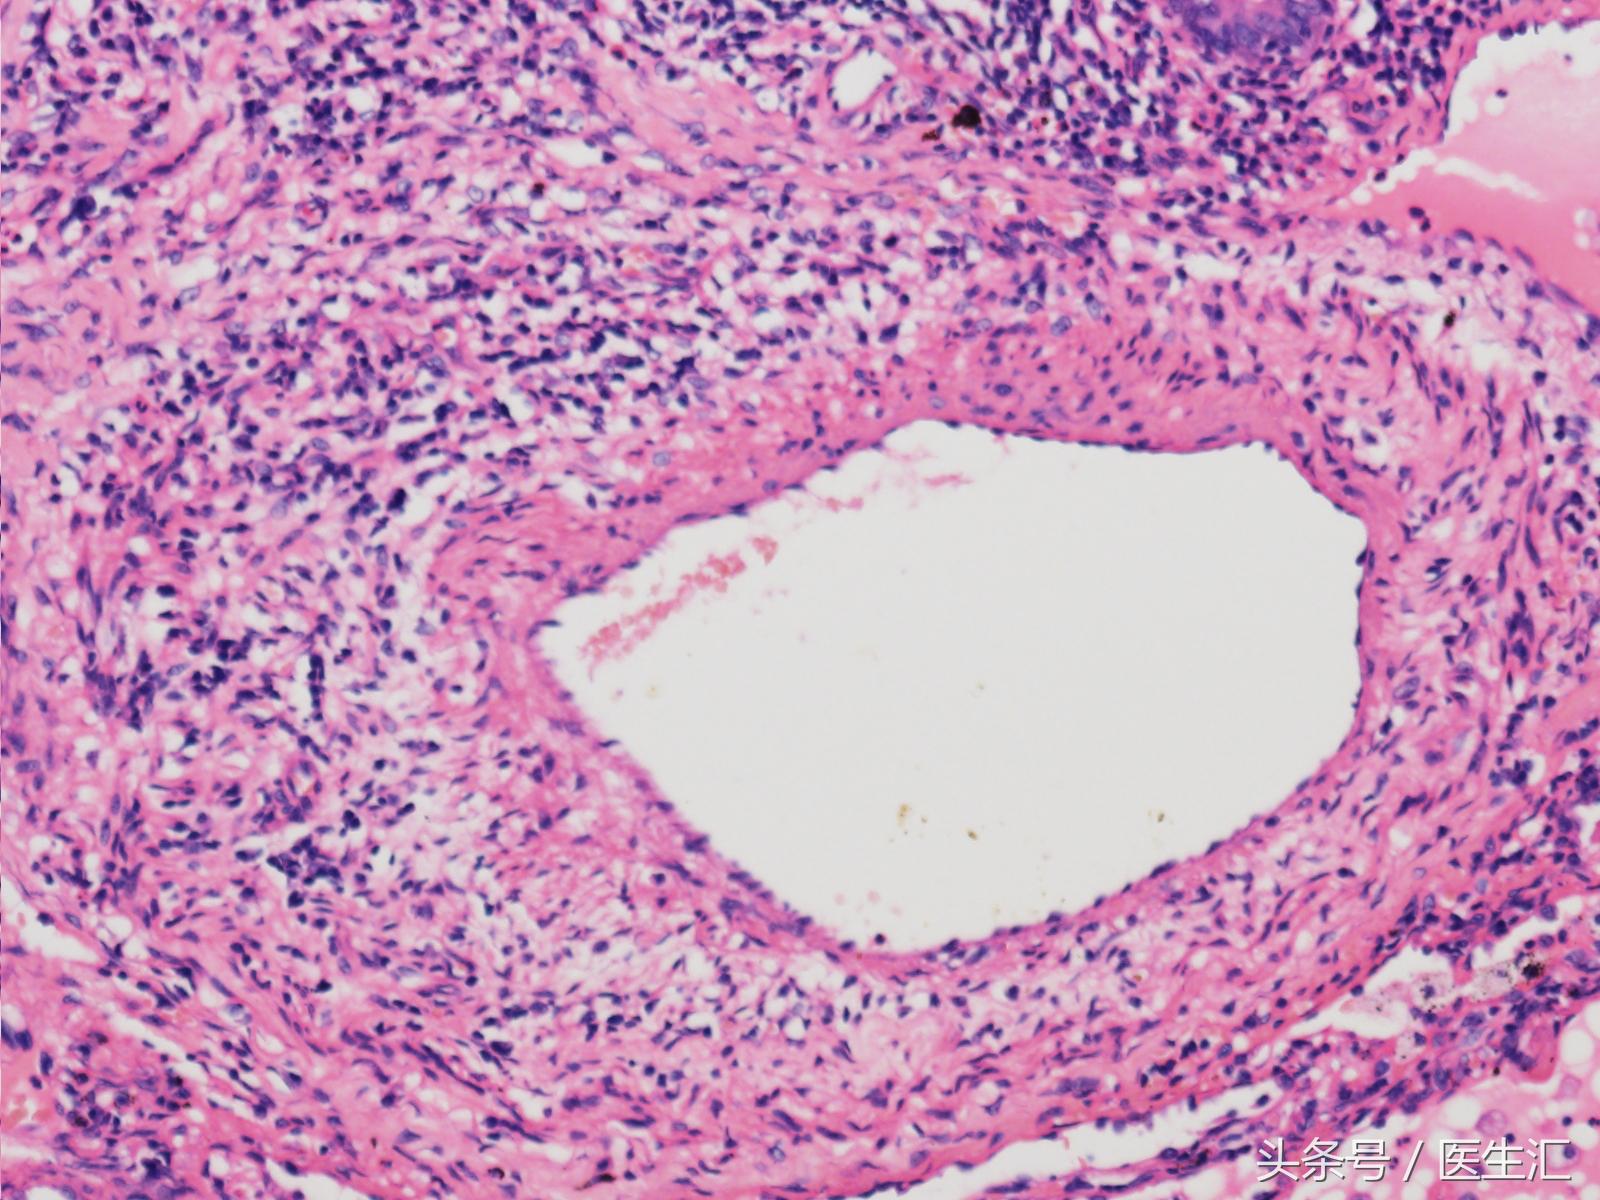

其后送病理检查,示:

结果如下:

根据结果可以看出,因为患者血管壁整体增厚,血管管腔狭窄,所以出现在肺里必定会引起肺动脉高压的表现,因为血管窄,所以肺血管的阻力是大大增加的。